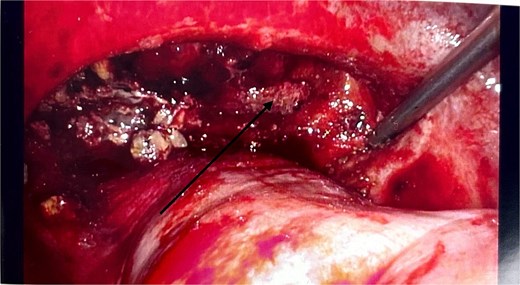

There were no other obvious signs of peritoneal or omental disease. About 2.6 L of haemoperitoneum with clots was drained during the surgery and the oozing cavity was packed with Surgicel haemostatic gauze, as shown in Fig. 4.

Intraoperative laparoscopic image showing the cavity packed with Surgicel haemostatic gauze (black arrow).